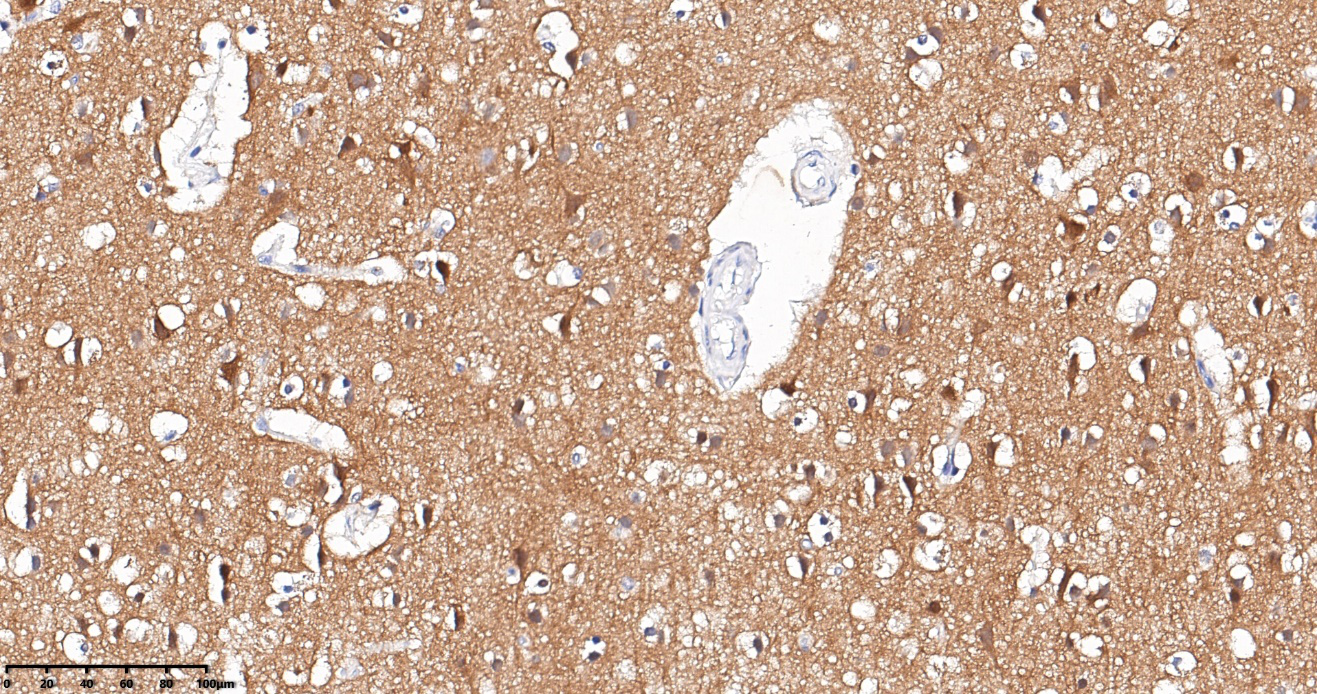

| 陽(yáng)性組織對(duì)照 | 腦組織 |

TRK(pan)腦組織免疫組化 30X